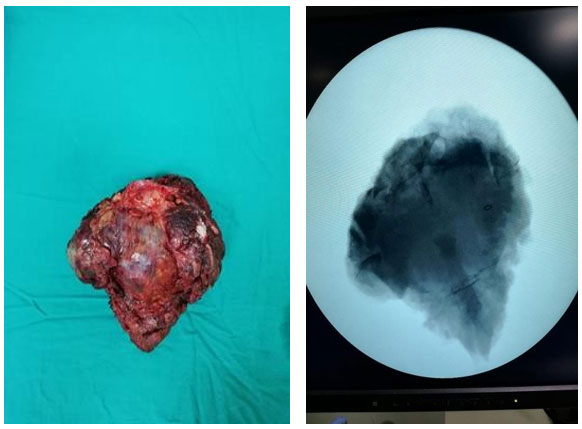

Ameliyat Esnası: Tümörün tek parça halinde çıkarılması sonrası rektum ve sakral kökler, uygulanan mesh ve titanyum plak görülmekte

Ameliyat Esnası: Çıkarılan tümörün klinik ve skopi görüntüsü